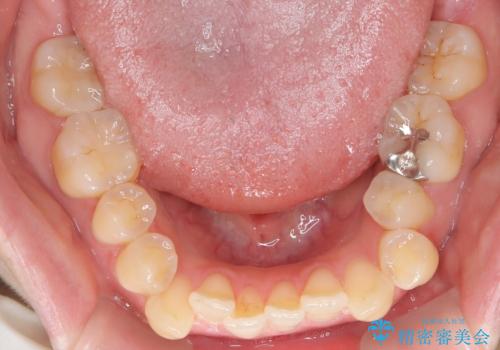

- 前歯のガタガタや八重歯の位置の乱れが気になっていた患者様に対して、ワイヤー矯正を行いました。矯正の過程で、スペースを確保するために上下左右の小臼歯を抜歯し、歯全体のバランスと機能性を考慮しながら理想的な歯列に仕上げました。

抜歯によって確保したスペースを活用し、効率的に歯列を整えました。前歯のガタガタと八重歯が解消され、自然で美しい仕上がりを実現しました。